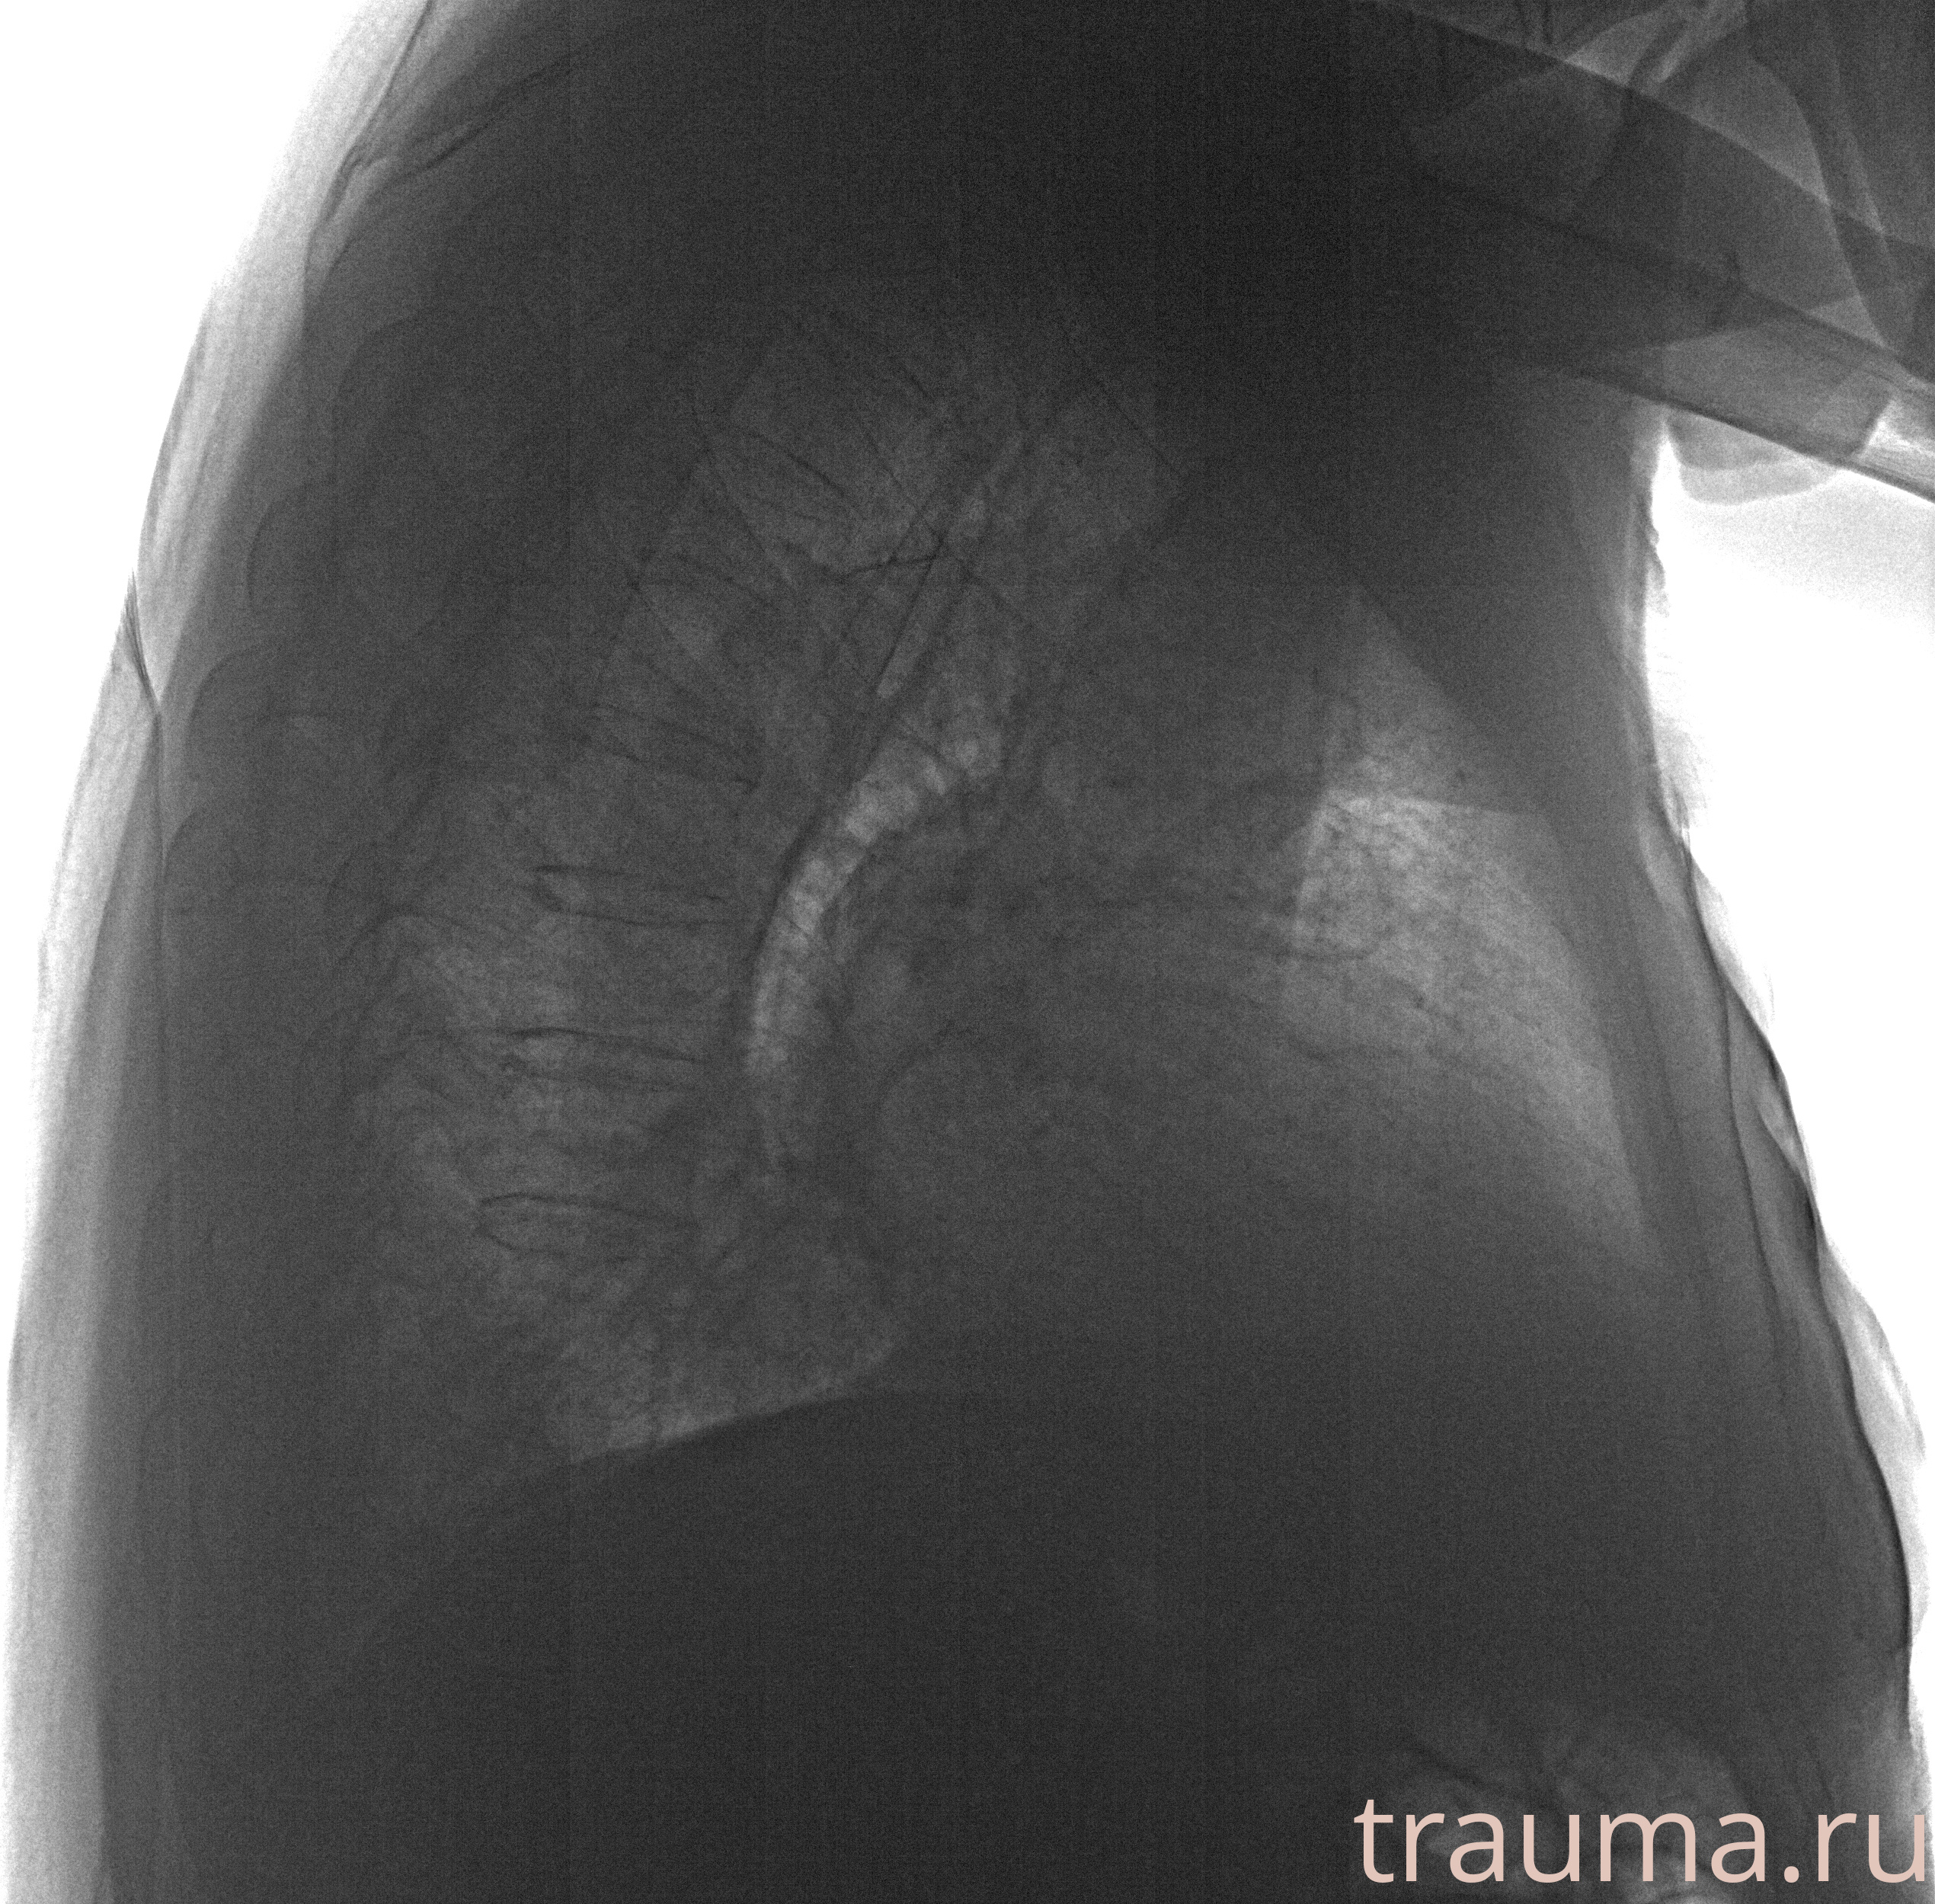

Рентгенограммы

Рентген на дому: по вашему адресу приезжает врач-рентгенолог, травматолог-ортопед с мобильным рентгеновским аппаратом, проводит диагностику травмы или заболевания, делает необходимые рентгенограммы, дает рекомендации по дальнейшему лечению. Получить качественные снимки в домашних условиях возможно благодаря уникальной методике, разработанной МосРентген Центром для института  Склифосовского